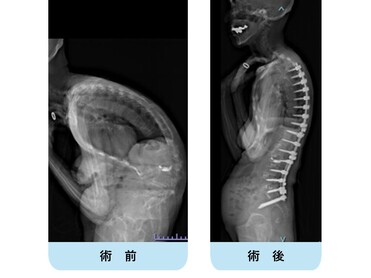

思春期特発性側弯症の全脊椎レントゲンで背骨が大きくSの字に曲がっています。最も曲がっている箇所は80°で、高度側弯に分類されます。後方からの脊柱側弯矯正術で真っ直ぐになっています。

また、側弯の患者さんは一般的にフラットバックと言って背骨の生理的後弯(背中の丸み)が失われています。この症例も胸椎後弯角は5°で典型的なフラットバックを呈しています(正常は20°~30°程度です)。この影響は頸椎の形態にも影響を及ぼし、この症例も頸椎が既に後弯(正常は前弯)しています。(黄色矢印)

ストレートネックという頸椎の前弯が消失して頸部の愁訴が出現する病態は広く知られていますが、更に変形が進行した頸椎と考えて下さい。

以前はこのフラットバック(生理的胸椎後弯の消失)を治すことは困難でしたが、当院では手術方法の様々な工夫により生理的胸椎後弯の復元を行っております。この症例は術後に胸椎後弯角が26°と改善しており、生理的な胸椎後弯が形成されています。さらに頸椎後弯にも良い影響を及ぼし、術後は頸椎前弯化が得られつつあるのが分かります。(黄色矢印)

他、側弯変形は必ず大なり小なりの回旋変形を伴います。脊柱の回旋変形は胸郭(肋骨)の回旋につながり、これにより側弯の患者さんは背中の片方が出っ張っています(多くは右)。リブハンプと言いますが、脊柱変形矯正によりこの回旋変形も改善します。この症例も術前に肋骨がかなり隆起していますが、術後にこの隆起がかなり減じているのが分かります。(赤色矢印)